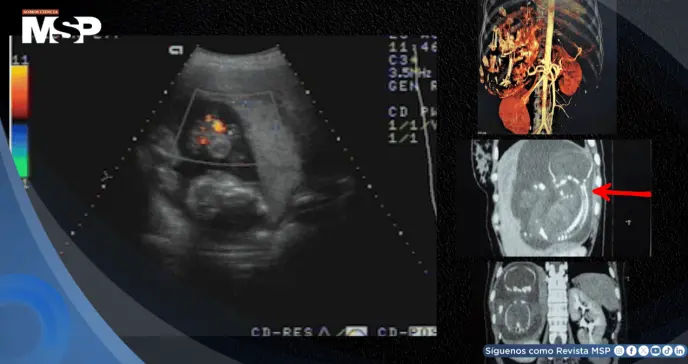

Este síntoma motivó la realización de estudios de imagen más exhaustivos en el Centro Médico MEDIC y el Hospital T? Du de Ciudad Ho Chi Minh. La ecografía abdominal reveló un feto de 23 semanas de gestación, con latidos cardíacos positivos, desarrollándose dentro del hígado de la paciente.

La confirmación definitiva llegó el 28 de agosto de 2007 mediante tomografía computarizada, que estableció sin lugar a dudas la presencia de un embarazo hepático de 23 semanas, localizado completamente dentro del parénquima del lóbulo hepático derecho.

Los estudios de angiotomografía computarizada multifocal con contraste revelaron detalles vasculares críticos: los vasos de la bolsa fetal se originaban directamente de la arteria hepática, y la placenta mostraba una adherencia significativa al tejido hepático, características que explicaban la viabilidad del embarazo pero que simultáneamente representaban un riesgo vital inminente.

Las imágenes diagnósticas permitieron caracterizar este raro embarazo abdominal. La masa fetal medía 12 x 15 x 17 centímetros, ubicándose en el abdomen, por debajo del diafragma derecho y dentro del lóbulo hepático derecho.

La placenta, con un grosor considerable de 47 milímetros, mostraba una invasión directa del hígado derecho y recibía su irrigación vascular principalmente de la arteria hepática derecha, configuración anatómica que convertía cualquier intervención en un procedimiento de altísimo riesgo por la vascularización extremadamente abundante.